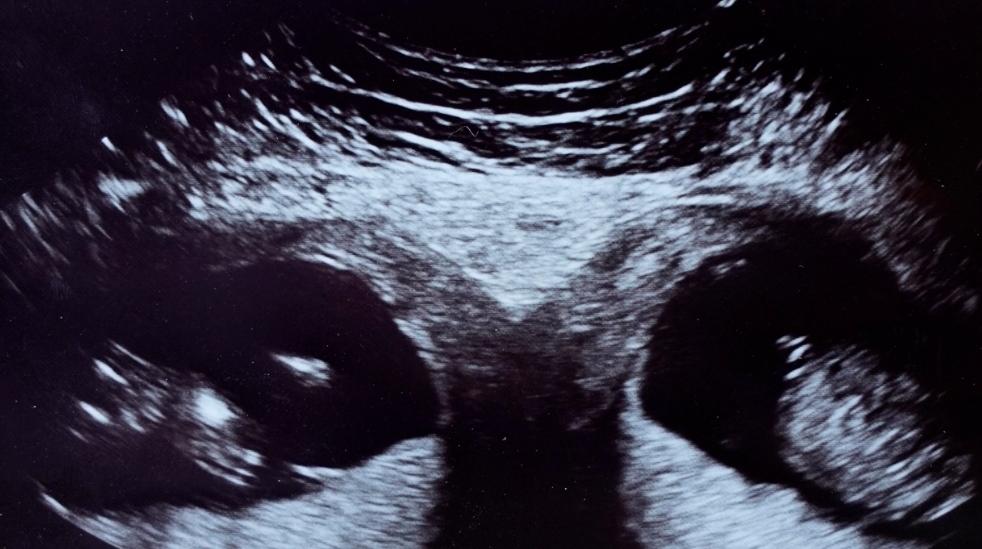

据英国《太阳报》2020年6月25日报道,一怀孕英国女子——凯莉·费尔赫斯特(Kelly Fairhurst)被检查出拥有两个子宫,且以每个子宫怀有一个这种方式拥有了双胞胎。

医生说凯莉这种情况非常罕见,她两个子宫里的孩子可能一模一样,这种几率只有五千万分之一。

凯莉和34岁的男友约书亚·邦迪(Joshua Boundy)是在凯莉12周检查时得知了这个消息。

阿玛·哈利勒(Asma Khalil)教授是伦敦南部图廷市圣乔治医院的产科专家,他告诉《太阳报》:“凯莉的子宫属于一种先天性畸形,有双子宫和两个独立的子宫颈,也可能有双阴道。”

“据估计,这种情况每3000名女性中就会有一人出现。世界上有记录的拥有这种子宫的女性生下同卵双胞胎的案例就更加罕见了。